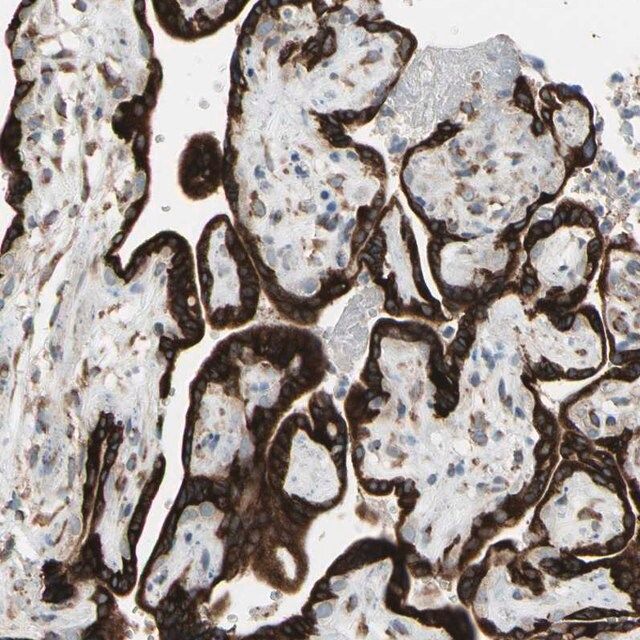

| Application【应用】 | All Prestige Antibodies Powered by Atlas Antibodies are developed and validated by the Human Protein Atlas (HPA) project (www.proteinatlas.org)and as a result, are supported by the most extensive characterization in the industry. The Human Protein Atlas project can be subdivided into three efforts: Human Tissue Atlas, Cancer Atlas, and Human Cell Atlas. The antibodies that have been generated in support of the Tissue and Cancer Atlas projects have been tested by immunohistochemistry against hundreds of normal and disease tissues and through the recent efforts of the Human Cell Atlas project, many have been characterized by immunofluorescence to map the human proteome not only at the tissue level but now at the subcellular level. These images and the collection of this vast data set can be viewed on the Human Protein Atlas (HPA) site by clicking on the Image Gallery link. To view these protocols and other useful information about Prestige Antibodies and the HPA, visit sigma.com/prestige. |

| technique(s) | immunoblotting: 0.04-0.4 μg/mL immunofluorescence: 0.25-2 μg/mL immunohistochemistry: 1:200-1:500 |